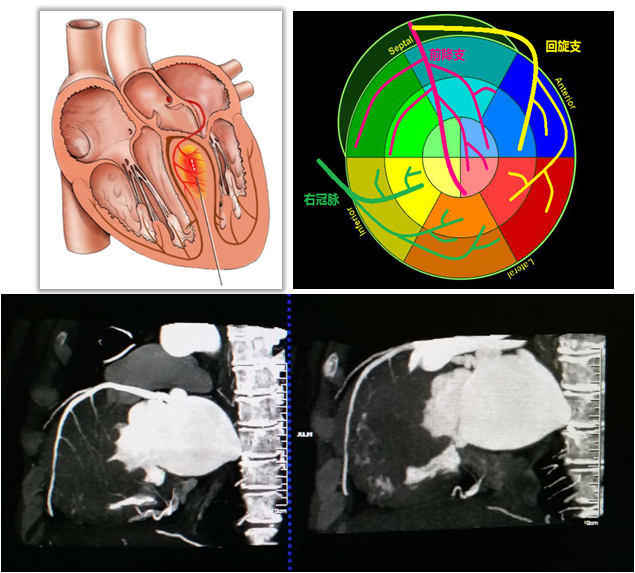

Liwen术式病例介绍

|作者:李静 刘丽文

|单位:空军(第四)军医大学西京医院